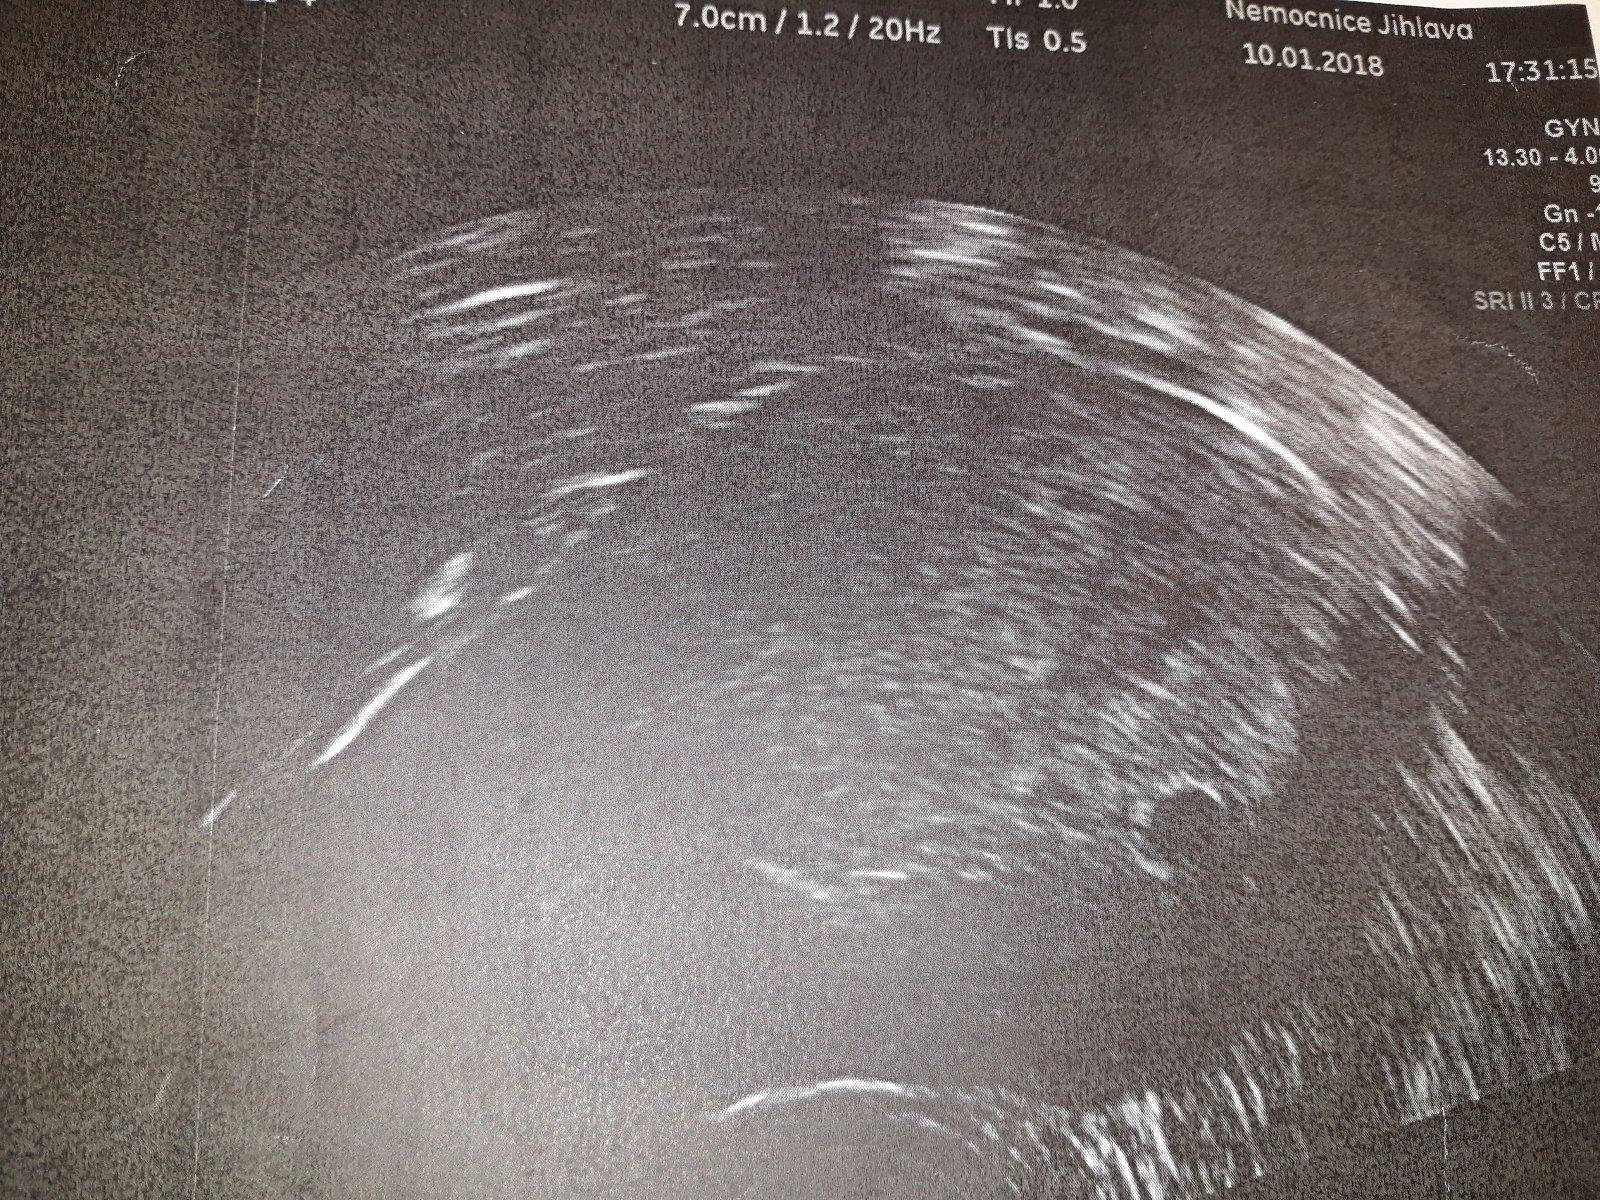

Holky, TT pozitivní? na UZ dnes vubec nic,ani gestační váček!! 😞 Prý jen hoodně vysoká sliznice. Krev na HCG nabráno, výsledky "až" v pondělí. Jsem nervozni.. že bych šla na gyndu, až moc brzy, hodně rané těhotenství? MÁTE ZKUŠENOST ??

Ahoj holky,dnesni kontrola super. Zatim jen dutinka, za tu jsem moc rada. 27.1.prvni tehu poradna. Vel.odpovida spise ovulaci,ale tak to jsme cekali,vetsi mereni az priste a podle toho se teprve udela termin porodu.